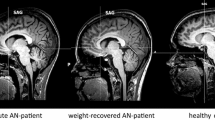

Group comparisons revealed a significant increase in MD in underweight AN relative to HC in a single white matter cluster of 8797 voxels, peak MNI coordinates: − 16, 12, 36 (L superior corona radiata). It was comprised of 18 white matter regions identified with the John Hopkins university atlas (Table 2). These regions included the corpus callosum, association fibers, namely the left sagittal stratum and external capsule, projection fibers such as the bilateral corona radiata (anterior, superior and posterior portions), left internal capsule (anterior, posterior and retrolenticular) and limbic fibers such as the bilateral cingulum and left fornix (Fig. 1). Post hoc examination of the component measures revealed that within this significant MD cluster, there was significantly increased RD and AD in underweight AN relative to HC (Fig. 2).

TBSS results comparing MD, AD and RD in underweight adolescents with anorexia nervosa (AN) versus age-matched healthy controls (HC). Significant tracts (p < .05) with underweight AN > HC are shown in orange. MNI coordinates, x = − 1, y = − 25. Underlying white matter skeleton shown in green. MD mean diffusivity, AD axial diffusivity, RD radial diffusivity

There were no significant differences between groups in FA. Mean FA and MD were extracted from the whole-brain white matter skeleton for each individual and are presented in Fig. 1 to provide an overview of individual differences.